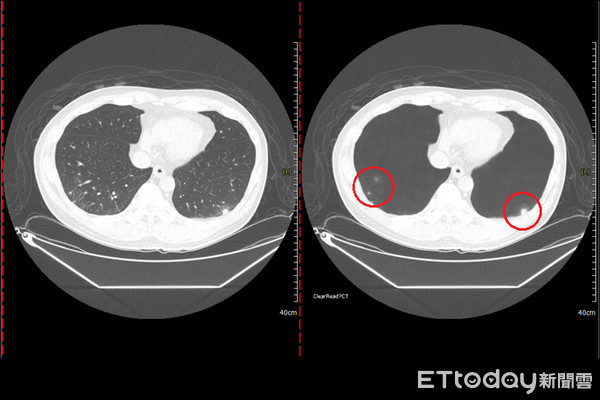

張克士表示,肺癌是台灣人的新國病,死亡率也最高,許多民眾初期沒什麼異狀,發現時都太晚了。加上傳統的胸腔X光片篩檢,難以發現1公分以下的結節,發現時多為晚期,影響治療效果,建議以低劑量電腦斷層,可以找到0.2~0.3公分的結節,加上院方引進AI辨識系統,去除血管顯影干擾,幫助醫師正確判讀、不眼花,大大提升準確度。

▲左圖為正常顯影,右圖為AI輔助判讀,去除血管的干擾。(圖/記者謝承恩翻攝)